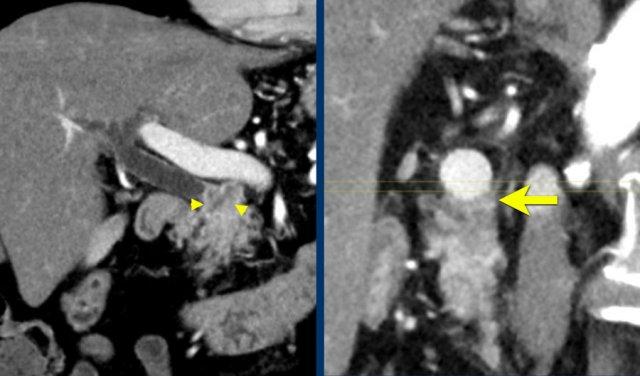

Hình tái tạo mặt phẳng đứng ngang (a) cho thấy một khối u nhỏ ở vùng bóng Vater (đầu mũi tên), gây tắc nghẽn cả ống mật chủ (CBD) và ống tụy (PD). Khi không có xâm lấn tại chỗ, tổn thương này được xem là có thể cắt bỏ được.

Tuy nhiên, hình CT axial (b) cho thấy phì đại của cung động mạch quanh tụy (các mũi tên), gợi ý mạnh hẹp đáng kể thân tạng.

Hẹp thân tạng được thể hiện trên hình MIP mặt phẳng đứng dọc (mũi tên trong c).

Dòng máu bàng hệ đến động mạch gan qua cung động mạch tụy-tá tràng (mũi tên nét đứt) được quan sát rõ trên hình MIP mặt phẳng đứng ngang (d).